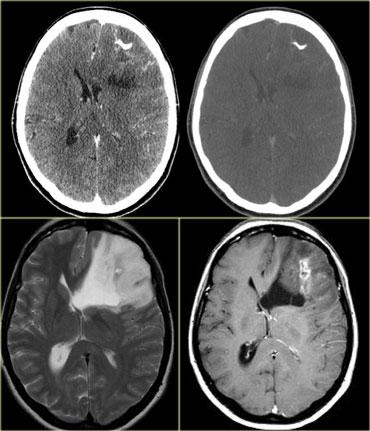

Hình bên trái là một số hình ảnh của các khối u có cường độ tín hiệu cao trên chuỗi xung T1W.

Ngoài cùng bên trái là hình ảnh của một bệnh nhân nhập viện vì đột quỵ tuyến yên (apoplexy).

Tín hiệu cao là do xuất huyết trong u tuyến yên đại thể (pituitary macroadenoma).

Bệnh nhân ở giữa có u nguyên bào đa hình thể (GBM), gây xuất huyết ở thể trai (splenium of the corpus callosum).

Bên phải là bệnh nhân có di căn từ u hắc tố (melanoma).

Cường độ tín hiệu cao là do hàm lượng melanin.

Hình bên trái là một số ví dụ về các khối u có cường độ tín hiệu thấp trên chuỗi xung T2W.

- Di căn u hắc tố có tín hiệu thấp trên chuỗi xung T2W do melanin.

- GBM có thể có tín hiệu thấp trên chuỗi xung T2W vì đôi khi chúng có tỷ lệ nhân-bào tương cao. Tuy nhiên, hầu hết GBM tăng tín hiệu trên chuỗi xung T2W.

- PNET thường có tỷ lệ nhân-bào tương cao. PNET chủ yếu nằm ở vùng não thất IV, nhưng một vị trí khác ít gặp hơn là vùng tuyến tùng.

- Di căn từ ung thư nhầy (mucinous metastases) có thể có tín hiệu thấp trên chuỗi xung T2W vì chúng thường chứa vôi hóa.

- U màng não (meningioma) thường có tín hiệu trung gian.

Chúng có thể có tín hiệu cao trên chuỗi xung T2W nếu chứa nhiều nước.

Chúng có thể có tín hiệu thấp trên chuỗi xung T2W nếu rất đặc và tăng sinh tế bào cao hoặc khi chứa vôi hóa.